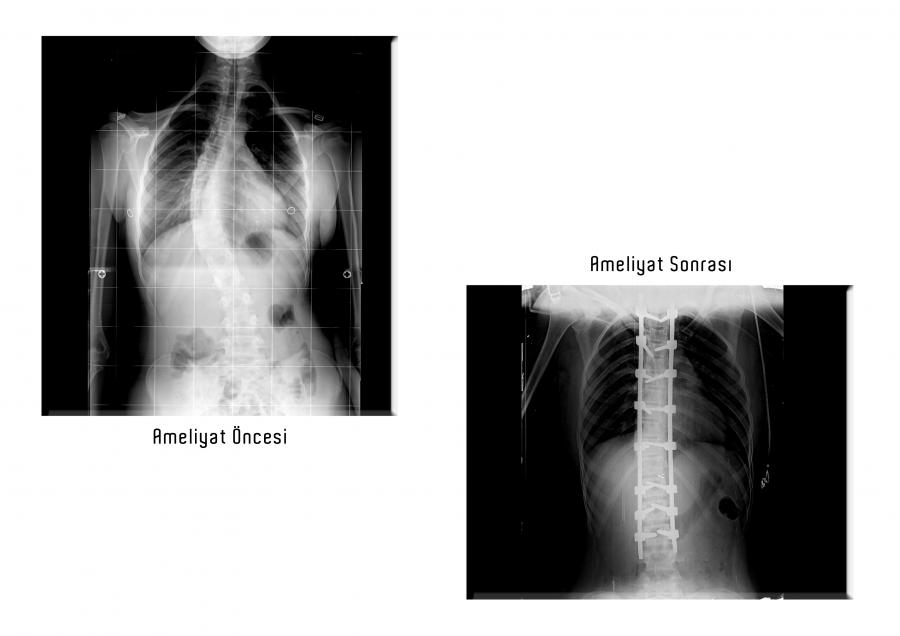

Omurga Eğriliği Olan Kız Çocuğu 5 Saatlik Ameliyatla Sağlığına Kavuştu

Hastanemize başvuran 14 yaşındaki kız çocuğu hastamızın, sırtında ve belinde uzun zamandır var olan ağrı, dengesizlik, vücudunda şekil ve duruş bozukluğu şikâyetlerinden mustaripti. Yapılan tetkiklerde hastamıza “Skolyoz Hastalığı” tanısı kondu. Türkiye’de çok nadir merkezde yapılabilen skolyoz ameliyatı, Ortopedi ve Travmatoloji Anabilim Dalı öğretim üyelerimizden Dr. Ögr. Üyesi Ali EREN başkanlığındaki ekip tarafından gerçekleştirildi. Operasyon sonrasında hastamız şifa ile taburcu edildi. Hastanemiz, bu tür nadir merkezlerde yapılabilen ameliyatlarla uluslararası arenada şifa merkezi olma yolunda emin adımlarla ilerlemektedir.

Skolyoz, omurganın göğüs veya bel bölgelerinde görülen yana doğru eğriliktir. Tek başına olabileceği gibi kamburluk ile beraber de görülebilir. Bu durumda kifoskolyoz olarak adlandırılır. En sık ergenlik çağındaki çocuklarda altta yatan bir sebep olmaksızın görülür. Özellikle ileri derece hastalık, kız çocuklarında çok daha sık görülür. Hastada kozmetik açıdan önemli sorunlara yol açabilir. Ağrı nedeni olabilir. İleri derece skolyoz akciğer hastalıklarına yol açabilir. Hastanın muayenesi ve radyografiler ile tanısı konulabilen skolyoz hastalığının radyografilerde ölçülebilen eğrilik açısı vardır. Temel olarak bu açıya göre hastanın tedavisi düzenlenir. İleri derece skolyoz için ameliyat gereklidir.